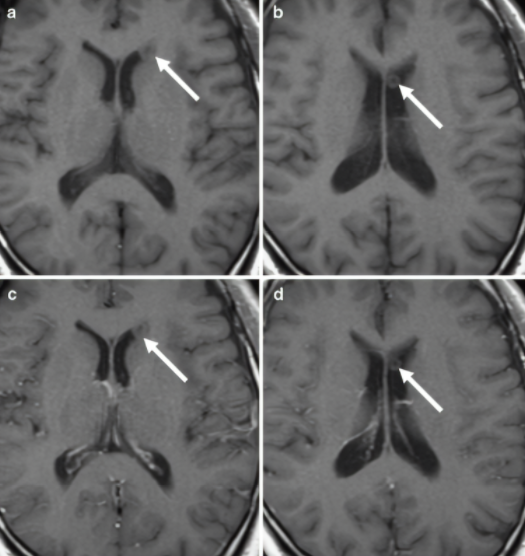

MR 表现:表现为室管膜下单个或多个结节样信号,体积往往比较小,即使多个大小也相当。T1WI 表现为结节样等信号,中心呈低信号,T2WI 表现为等信号,中心高信号,FLAIR 呈稍高信号,增强扫描不会出现强化。

2 例单发侧脑室环状结节,增强检查均未见强化